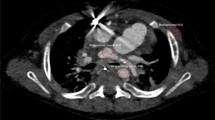

CT has become a valuable modality in evaluating the complex anatomic findings associated TGA. CT can be used to evaluate the origin and course of the great arteries, the presence and size of the PDA and/or PFO, and any associated anomalies such as LVOT obstruction and aortic coarctation [70]. DSCT examination of a 3-day-old patient with TGA is shown in Fig. 5. CT protocol and radiation dose are summarized in Table 7.

DSCT images in a 3-day-old patient with TGA. Aorta (yellow arrow) arises from the morphologically right ventricle and is located anteriorly of pulmonary artery (blue arrow) (a, b). Pulmonary artery (blue arrow) arises from morphologically left ventricle (a, c). Presence of large ventricular septum defect (d) (yellow arrow). Volume rendering reconstructions in superior view with (e) and without aorta (f)